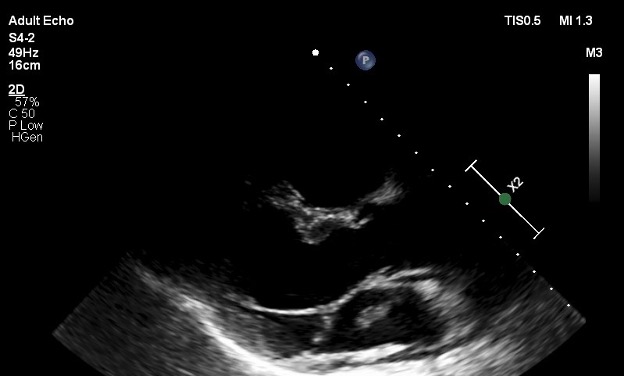

45 yaşlı kişi xəstə sağ ayaqda anidən yaranmış şişkinlik, kəskin ağrı, təngnəfəslik şikayəti ilə xəstəxanamızın təcili tibbi yardım şöbəsinə müraciət etmişdir. Xəstə 10 il əvvəl mielit keçirmiş və sağ aşağı ətrafın hissəvi parezi mövcuddur. Passiv həyat tərzi keçirdiyini, günün çox hissəsini evdə hərəkətsiz vəziyyətdə olduğunu qeyd edir. Xəstəyə dərhal exokardioqrafiya olundu və sağ boşluqların genişləndiyi, ağciyər arteriyasının sistolik təzyiqinin artmış (50mmHg) olduğu görüldü. Daha ətraflı müayinə zamanı sol və sağ qulaqcıq daxilində də hərəkətli kütlənin olduğu görüldü. Xəstəyə transezofageal exokardioqrafiya tövsiyə edildi, lakin xəstə bu müayinədən imtina etdi. Aşağı ətraf venalarının doppler müayinəsi zamanı sağ dizaltı venanın kəskin trombozu aşkarlandı. Sol və sağ qulaqcıq daxilindəki hərəkətli kütlənin tromb (Şəkil 1,2 və 3) ola biləcəyi düşünüldü və xəstə hospitalizasiya edildi. Xəstəyə gündəlik 30 mq (15 mq x 2 dəfə) rivaroksaban başlanıldı. Sağ aşağı ətraf üçün kompression corab təyin edildi. Müalicənin beşinci günü təkrari exokardioqrafiya olundu (Şəkil 4 və 5). Bu zaman görülən hərəkətli kütlələr görülmədi, sağ mədəciyin ölçüləri normallaşmış, ağciyər arteriyasının sistolik təzyiqi isə 35mmHg-na qədər enmişdir. 21 gün sonra rivaroksabanın dozası gündəlik 20 mq təyin edildi. Sağ aşağı ətrafda hissəsi parez olması səbəbindən rivaroksaban müalicəsi qeyri-müəyyən zamana qədər davam etdiriləcək.